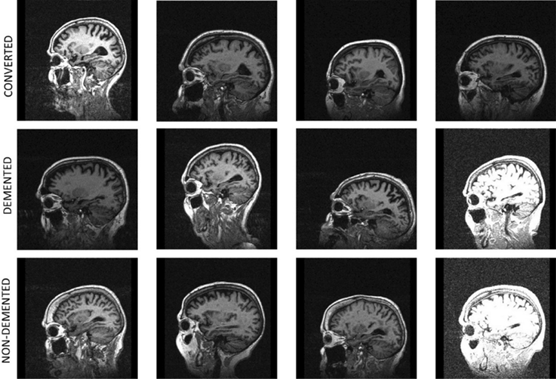

Dataset

The OASIS-2 dataset contains longitudinal MRI scans of elderly subjects, captured over multiple sessions. Each subject is labeled using Clinical Dementia Rating (CDR) scores. Subjects fall into four groups: Healthy (CDR=0), MCI-1 (CDR=0.5), MCI-2 (CDR=1), and Early AD (CDR≥2) [2]. All scans go through skull stripping, spatial alignment, and intensity correction. This dataset is widely used in research because of its quality and open access [10].